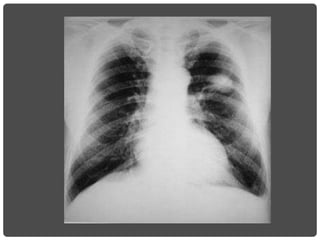

ASMA BRONQUIAL

Signos de atrapamiento aéreo

HIPERCLARIDAD BILATERAL

SIGNOS DE HIPERINSUFLACIÓN

• Descenso y aplanamiento de los diafragmas.

• Senos costofrénicos tienden a desaparecer.

• Aumento de tamaño de los espacios claros

retroesternal y retrocardíaco.

• Costillas horizontalizadas y espacios intercostales

ensanchados.

• Columna arqueada: cifosis pronunciada.

• Esternón protruido. Tórax en tonel.

• Trastornos vasculares: hilios grandes, disminución

de la vasculatura periférica, corazón en gota.